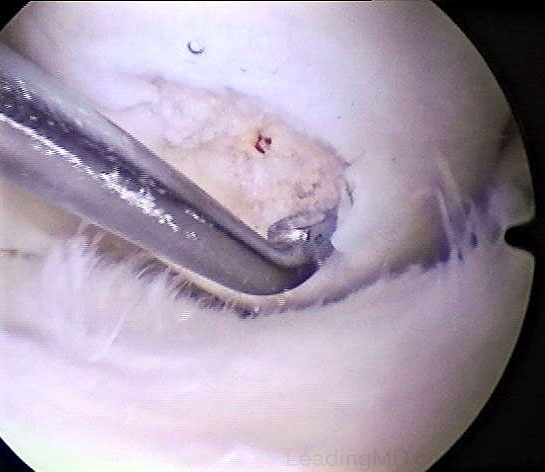

Image of cartilage defects

Microfracture is a surgical

technique that has been developed to treat chondral

defects, which are damaged areas of articular cartilage

of the knee. It is a common procedure used to treat patients

with full thickness damage to the articular cartilage that goes

all the way down to the bone.